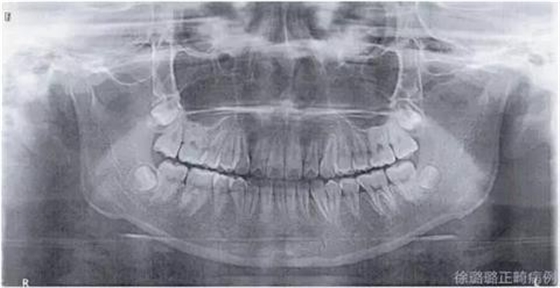

影像學(xué)檢查

360截圖20170120124727674.jpg

X 線檢查:替牙列,上頜雙側(cè)尖牙埋伏阻生(含牙囊腫),四顆第三恒磨牙牙胚存在。

360截圖20170120124736347.jpg

前牙 CT 檢查:上頜雙側(cè)尖牙埋伏阻生——雙側(cè)尖牙的牙冠均在側(cè)切牙根方的唇向位。